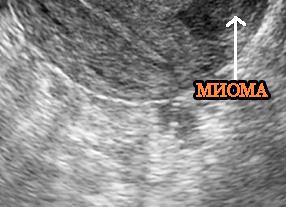

Постановка диагноза не представляет затруднений при увеличенных размерах матки, маточных кровотечениях, деформации матки узлами миомы. Обычного гинекологического обследования на кресле и проведения УЗИ органов малого таза достаточно для постановки диагноза. Миому можно обнаружить прощупыванием матки через переднюю брюшную стенку.

- УЗИ органов малого таза при помощи влагалищного датчика. Для улучшения визуализации исследование проводится с наполненным мочевым пузырем. Этот метод высокоинформативен, позволяет выявить точные размеры и форму опухоли.

- УЗИ органов малого таза . Проводится при помощи влагалищного датчика. Для улучшения визуализации исследование проводится с наполненным мочевым пузырем. Данный метод высоко информативен, позволяет выявить точные размеры и форму опухоли;

Вид на УЗИ

УЗИ при данном заболевании основано на стандартных принципах диагностики. Проводится через влагалище и переднюю стенку брюшины.

Если говорить о характеристиках, то они имеют следующие признаки:

- округлость опухоли;

- разнородность структурного наполнения;

- четкость наружных контуров и границ;

- слабеющий сигнал ближе к краю аномалии и усиливающийся в зоне ее центральной части.

Миома матки при ультразвуковом обследовании

Наиболее эффективная и информативная методика исследования – это ультразвуковое исследование. Принцип работы основан на принципе эхолокации. Датчик осуществляет ультразвуковые колебания, которые сразу же отображаются на экране.

Специалисты смогут увидеть, как выглядит миома, где локализуется и детально изучить сечение матки. Ультразвуковое исследование является полностью безвредной методикой, потому что излучение внутренних органов не превышает более 0,1% от всего времени.

Как выглядит миома на УЗИ

Самым информативным методом диагностирования заболевания, является УЗИ диагностика – метод эхографии. Для выявления топографического месторасположения узелковых новообразований применяют УЗИ томограф, позволяющий получить трехмерное изображение.

На экране отчетливо виден эндометрий матки (слизистая оболочка). Она выглядит, как другая структура в виде светлых полос. В центре находятся миоматозные образования. Темное пространство указывает на воспалительный процесс со скоплением крови или воспалительной субстанции.